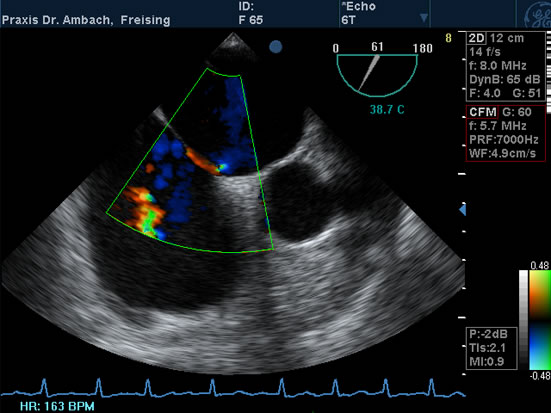

TEE - 2